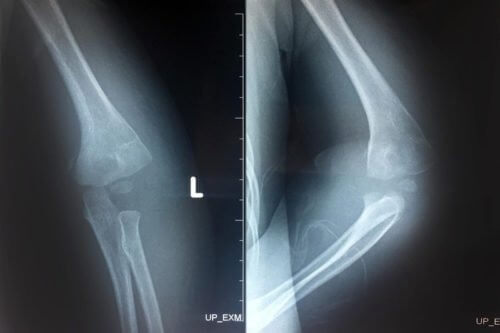

Khi bị gãy lồi cầu ngoài xương cánh tay người bệnh có thể nhận thấy phần ngoài của khuỷu tay bị sưng và biến dạng, xuất hiện vết bầm tím, khó khăn khi cử động. Để chẩn đoán chính xác vị trí gãy cũng như mức độ di lệch phải tiến hành chụp X-quang khuỷu tay, và có thể bao gồm cả siêu âm Doppler mạch máu trong trường hợp nghi ngờ mạch máu cũng bị tổn thương.

Bó bột bàn tay: Được chỉ định cho trường hợp gãy lồi cầu ngoài xương cánh tay không bị di lệch hoặc di lệch ít (độ 1, 2). Người bệnh được đặt khuỷu tay ở tư thế gập 90 độ, cẳng tay ngửa 60 độ và thực hiện bó bột. Sau đó cứ 2 tuần lại chụp X-quang 1 lần để kiểm tra tình trạng.

Phương pháp nắn kín + xuyên đinh qua da: Được chỉ định với các trường hợp gãy di lệch độ 1 & 2. Bác sĩ tiến hành nắn kín ổ gãy qua da bên dưới màn tăng sáng rồi thực hiện cố định thông qua 2 đinh được xuyên từ bên ngoài vào, sau đó kết thúc bằng nẹp bột cánh tay.

Phương pháp mở ổ gãy nắn và xuyên đinh: Được áp dụng với các trường hợp gãy di lệch độ III. Thường áp dụng khi biện pháp nắn kín với xuyên đinh qua da thất bại, gãy xương hở, hoặc người bệnh có dấu hiệu bị biến chứng thần kinh, mạch máu. Các bác sĩ sẽ tiến hành mổ ở mặt ngoài của khuỷu để mở ổ gãy, sau đó thực hiện nắn chỉnh, cố định ổ gãy bằng cách xuyên đinh từ bên ngoài vào (có thể để đinh ở trong hoặc bên ngoài da). Sau đó người bệnh được khâu phục hồi thần kinh mạch máu (nếu bị tổn thương), rồi nẹp bột.

- Chụp X-quang để kiểm tra tình trạng của ổ gãy.

- Sau 1.5 – 2 tháng thì tháo bột và chụp X-quang để xem quá trình liền xương.